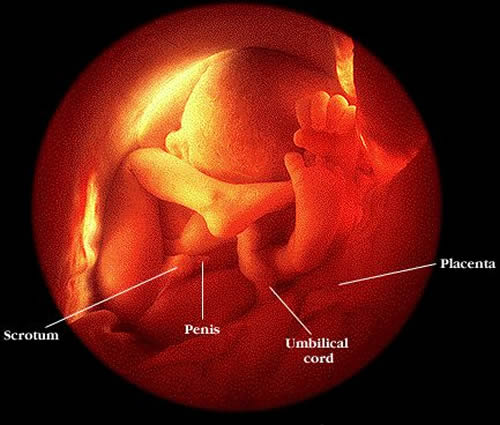

"人之初" 的第一日~

到最後只有一個精子,通過三關(丘細胞、卵外透明帶、及卵膜)的比賽後,脫了層外皮及粒腺体 (所以人的粒腺体全是由母糸來的),並丟了尾巴後,完成交付男方二十三個染色体的任務。

受精場所是輸卵管中空地最廣的 "壼腹部"。

受精卵在輸卵管分裂及成長,由桑椹期 (morula)、再成為囊胚期(blastocyst),大約要到第五天,才會回到子宮腔 ,又在宮腔游走二至三天,脫出透明帶 (zona pellucida) ,孵化後(hatched)著床,成為母子一体的狀態。

這時胚胎就自我分化出"胎盤'來接受母体營養,因而有胎盤素(HCG)出現在母血及尿液中,也只有到此時才可能被驗出是否有孕。